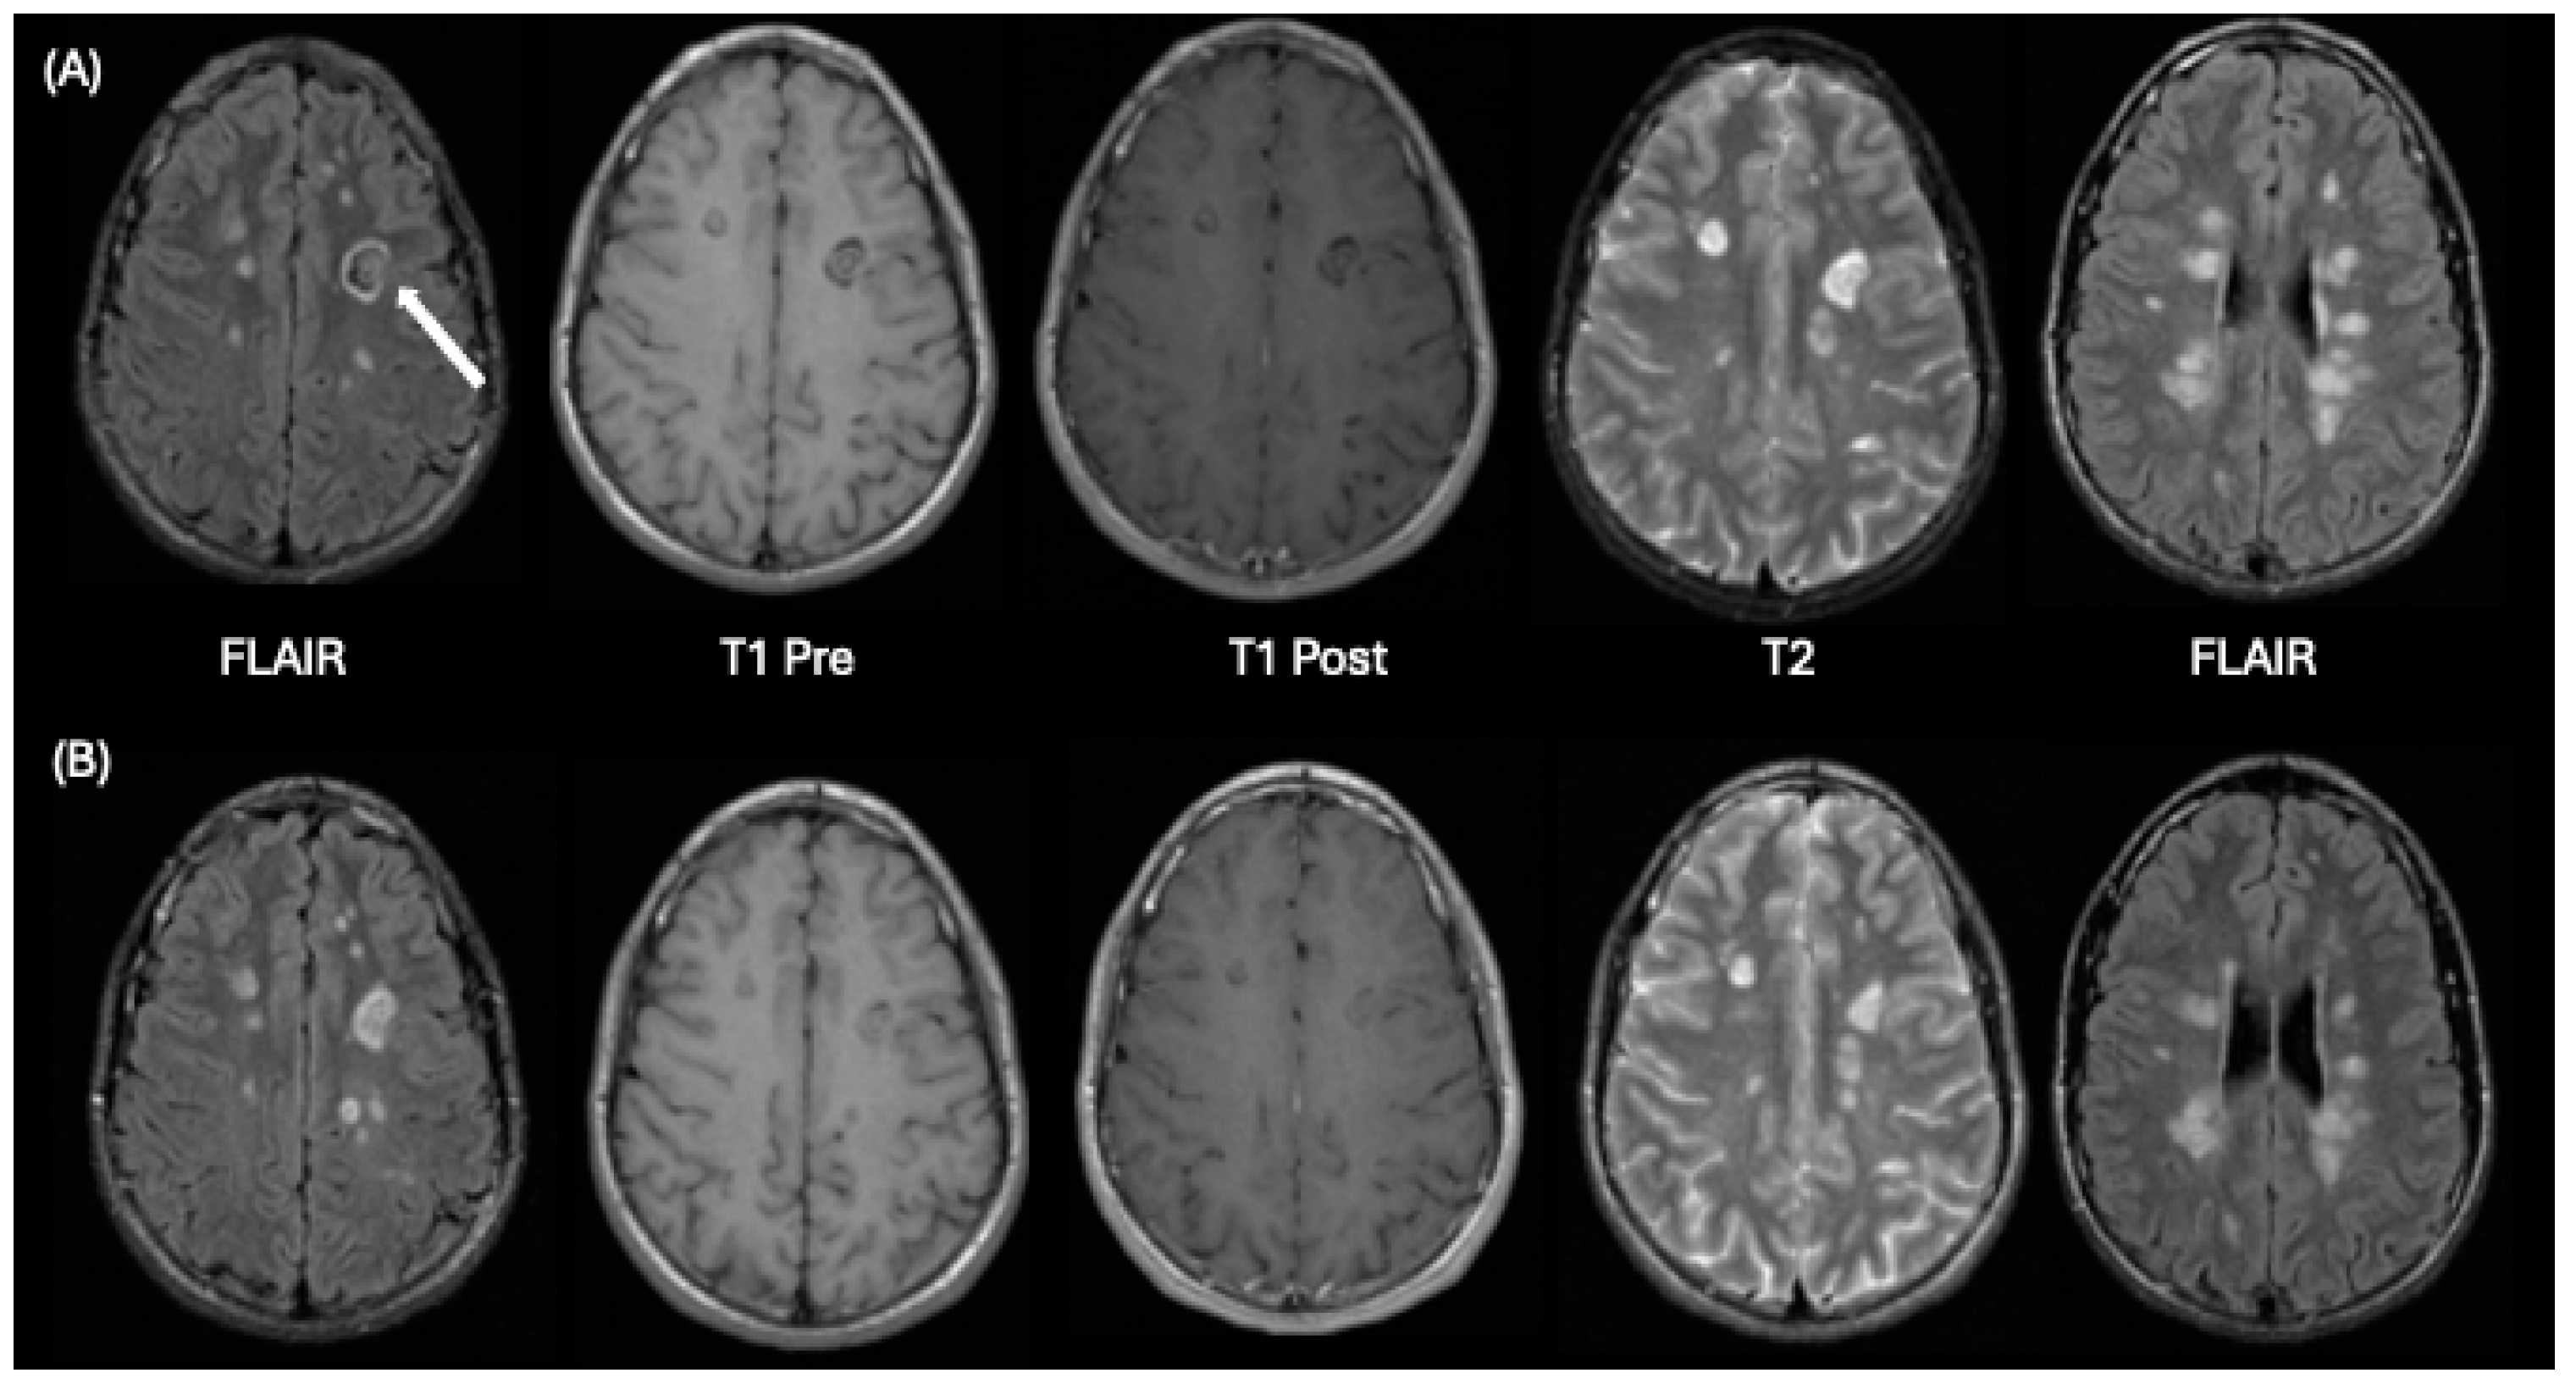

| ADEM | Typically, Monophasic following infection or vaccination | Centrum semiovale, thalamus, basal ganglia, cerebellum, brainstem; bilateral involvement; spinal cord involvement | Inconsistent lesion enhancement: if present, most lesions show enhancement | Asymmetric white matter, but symmetric deep gray matter lesions with borders not well-defined; variable sizes, larger than 2 cm; Similar age of lesions |